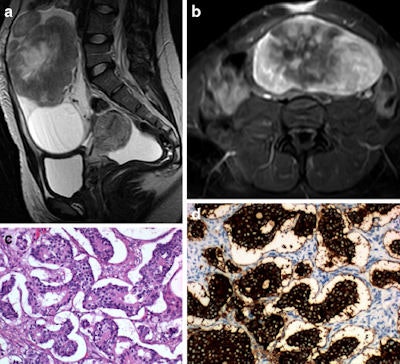

Endometrial NE tumors are very rare and are usually small cell carcinoma or adenocarcinoma with NE differentiation. Regarding other tumors, ultrasound, CT, PET/CT, and MRI remain the most commonly used imaging tools, but octreotide scans, which is a type of somatostatin analogue scintigraphy that assesses relevant receptor expression in vivo, may be useful for typical and atypical carcinoids. As a note, patients with negative octreotide scans should not be considered for somatostatin analogue therapy and typically show better responses to chemotherapy schemes, according to the researchers.

More specifically, when it comes to imaging, for the cervix, uterus, and adnexa, ultrasound using both transabdominal and transvaginal probes plays a crucial role in the initial diagnosis, and CT or PET/CT helps detect nodal and distant metastases.

MRI may be used to characterize indeterminate adnexal masses and for pretreatment staging purposes; it may also replace CT in the staging of adnexal tumors in young females and patients who are pregnant, have renal insufficiency, or are allergic to iodinated contrast. In the even rarer NE tumors of the vagina and vulva, MRI is also used for staging, along with CT.